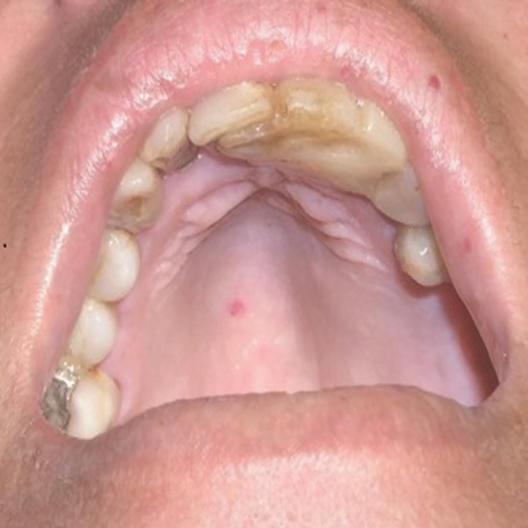

A clinical guide to oral manifestations and diagnosis of limited systemic sclerosis: a case report

Vanessa Carvajal Soto

Helen Heloene Rosa

Marcelo Carlos Bortoluzzi